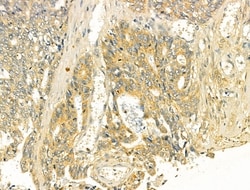

Invitrogen™ TOMM40 Polyclonal Antibody

Antibody detects endogenous levels of total TOM40.

| Immunohistochemistry (Paraffin), Western Blot | |

| A synthesized peptide derived from human TOMM40(Accession O96008), corresponding to amino acid residues R173-Q223. | |